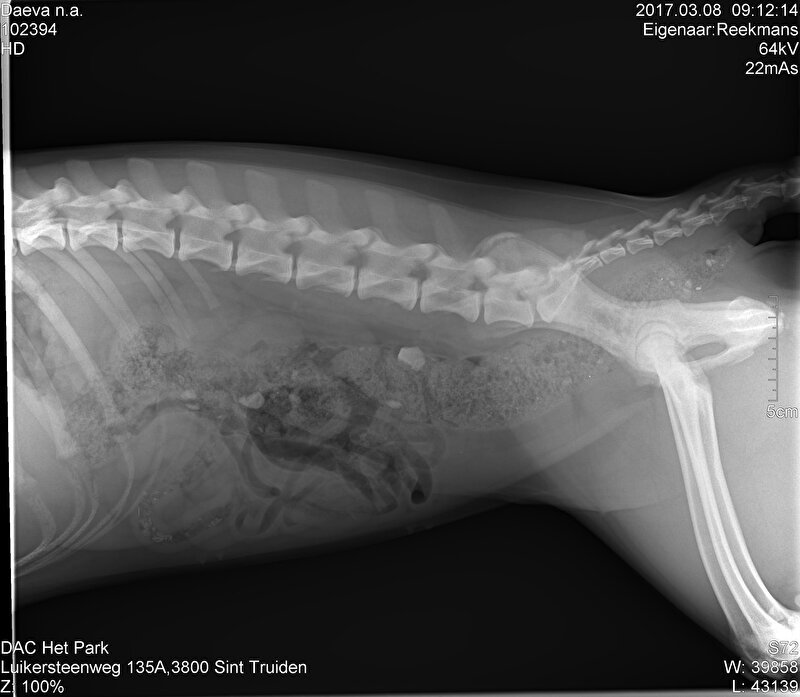

Elleboog gewricht gebroken bij een duik in het water, keurig 3 schroeven in geplaatst.. schroeven afgebroken na een weekEn dat terwijl hij bench rust had en 4 x per dag kort naar buiten.

Bij een volgende operatie zijn er grotere schroeven in geplaatst waar het helemaal goed mee is genezen en we hebben nogsteeds een blije hond